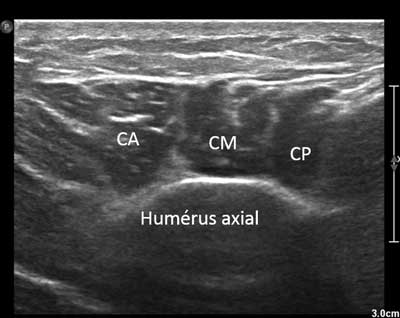

It swathes and stabilizes the glenohumeral joint and consists in three branches converging towards the lateral tuberosity of the proximal humerus (Figure 17) [2].

Figure 17

Axial view of the distal and lateral part of the deltoid muscle. CA: Anterior chief, CM: Medium chief, CP: Posterior chief.

A lesion is observed in 0.3% to 9.2% of rotator cuff tears, usually in its middle portion. After (massive) cuff rupture, two mechanisms may occur: ascension of the humeral head with subacromial impingement possibly leading to avulsion; Lateral subluxation of the humeral head causing an impingement between the greater tubercle and the deep surface of the myotendinous junction [12].

In case of sports injuries, most of the lesions on anterior and middle portions of the Deltoid (motor sports, contact sports, weight training) (Figure 18) [13]. Ultrasound allows an anterior, middle and posterior optimal study of its muscles’ insertions and its acromial and humeral enthesis where apatite deposits may lay.